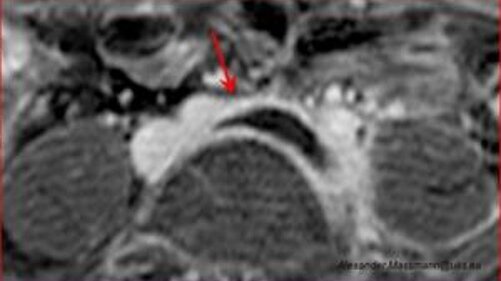

Die röntgenstrahlenfreie Magnetresonanztomografie (MRT) des Beckens zeigt die mit einem Pfeil markierte spitz zulaufende Thrombose (schwarze schnabelförmige Struktur) in der Beckenvene bedingt durch eine zugrundeliegende Beckenvenenkompression (May-Thurner).